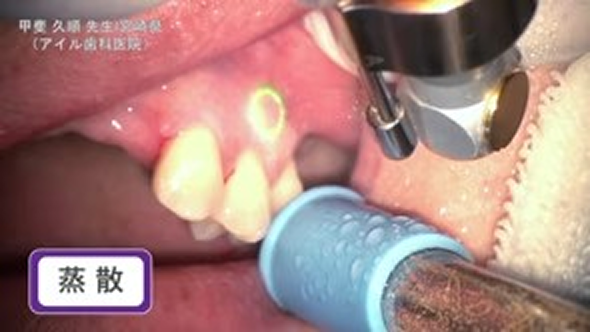

臨床例:炭酸ガスレーザーPRO+/Lite+(最大出力5~7W)を使用した先生の臨床例です。

蒸散